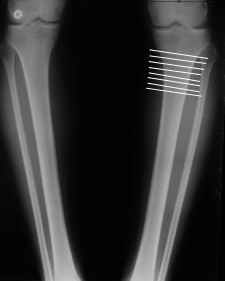

Вот ещё картинки, которые отправлял в Ортопод. Коррекция кривизны и удлинение на 3 см.

4. Если внимательно посмотришь на рентгенограммы, то в зоне перелома малоберцовой кости она втягиваетсмя внутрь, таким образом немного уменьшая объем тканей по внутреннему контуру. Причем чем выше - тем эффектнее. Не надо только совсем высоко лезть - там перонеус. Многих пайциенток это тоже смущает. Так что решаем проблему комплексно. На это, кстати, особо упирает Казбек Кудзаев.